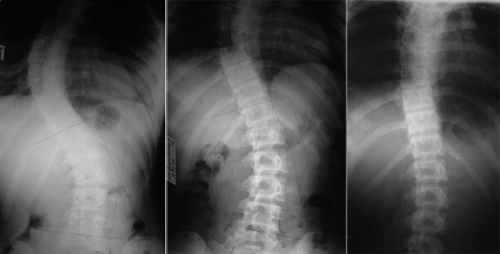

Для определения угла наклона используется метод Кобба. Сначала отмечаются линии с наименьшим и наибольшим изгибом, затем к ним проводят перпендикуляр. Угол измеряется в точках их пересечения.

При искривлении 1 степени признаки заболевания не проявляются при первичном осмотре. Диагностика осуществляется с помощью рентгенографии грудного и поясничного отделов позвоночника в различных проекциях. Для 2 степени деформации диагноз устанавливается на основе результатов осмотра, при этом ось позвоночника может отклоняться влево или вправо. Изгиб сохраняется при наклонах туловища. Пиковая часть правостороннего изгиба, как правило, располагается на уровне 10–12 грудных позвонков. Верхняя часть деформации находится в области Th6, а нижняя — L1–L2.